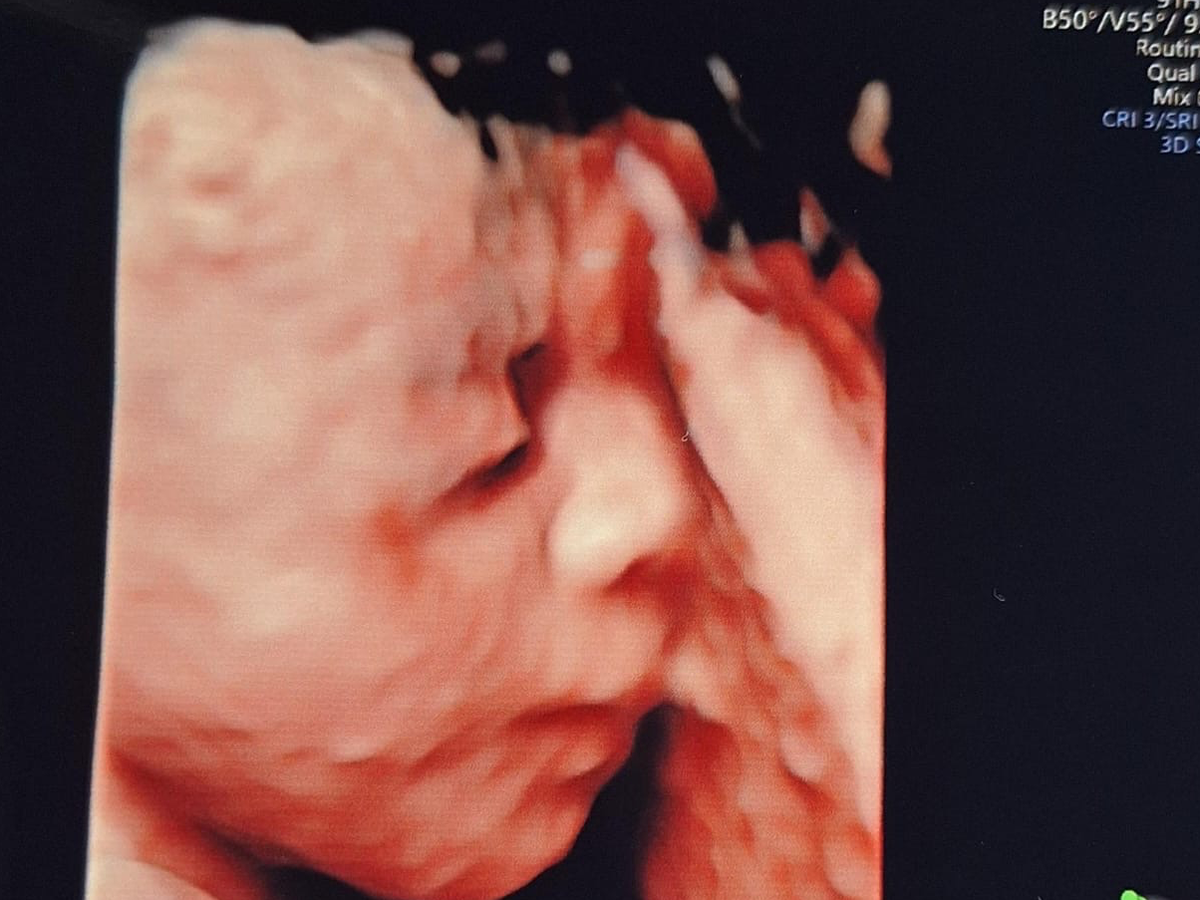

Hola mi nombre es Einar Nicolás y aún me encuentro en la pancita de mamá, hace poco me diagnosticaron una condición llamada Pentalogía de Cantrell lo que provoca que mi hígado, intestino y corazón se desarrollen fuera de mi cuerpo. Mamá y Papá descubrieron una clínica donde pueden atender esta condición y darme una oportunidad de vida, pero estas cirugías que necesito son muy costosas por eso están recaudando fondos. ¡Gracias por tu ayuda!

Hello, my name is Einar Nicolás and I'm still in mom's belly, I was recently diagnosed with a condition called Cantrell's Pentalogy which causes my liver, intestine and heart to develop outside my body. Mom and Dad discovered a clinic where they can take care of this condition and give me a chance at life, but these surgeries I need are very expensive that's why they're raising funds. Thank you for your help!